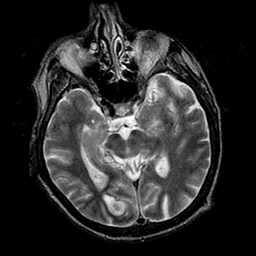

ตรวจร่างกายทั่วไปและการตรวจทางทางระบบประสาท และการทำเอ็กซเรย์คอมพิวเตอร์ (CT scan) ในบางรายหากสงสัยว่าอาจเป็นอย่างอื่น

แพทย์ที่ตรวจอาจให้ตรวจสมองด้วยคลื่นแม่เหล็กไฟฟ้า(MRI) แทนการตรวจเอ็กซเรย์คอมพิวเตอร์

การทำ CT scan ของสมอง

จะช่วยให้แยกได้ระหว่างเส้นเลือดตีบหรือแตก ซึ่งการรักษาจะต่างกันไป